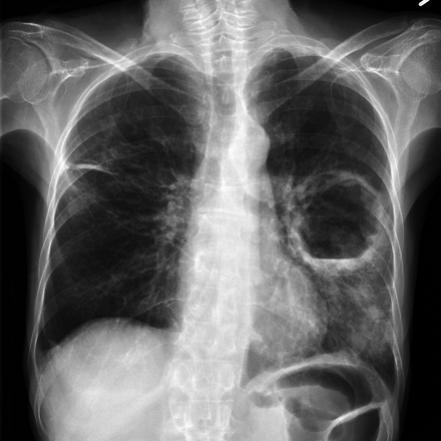

canon ball lesion

cyst hydatic

Pulmonary Abscess

Lung abscess

Absceso pulmonar

Cavity

absceso pulmonar o quiste

ascesso polmonare